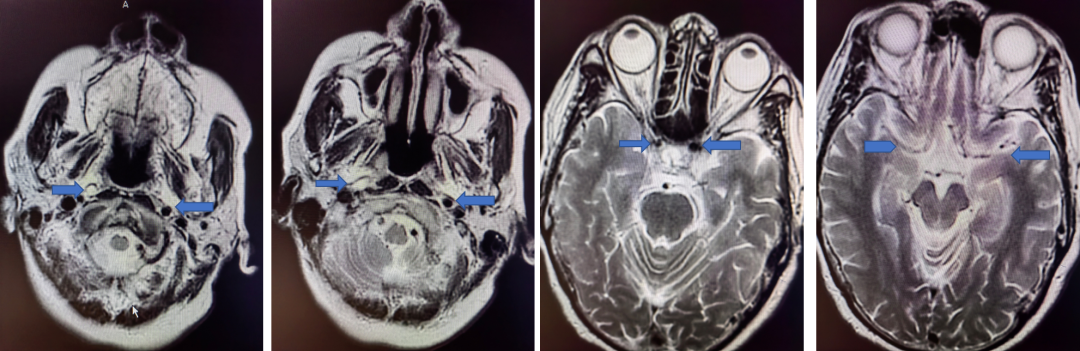

MRI+DWI

重要影像结论:右侧放射区、右侧基底节区、左侧额叶近大脑镰处多发急性梗死。

MRI  T2相

重要影像结论:右侧颈内动脉岩骨段管腔内不清晰,眼动脉段远端管腔较对侧明显缩小。